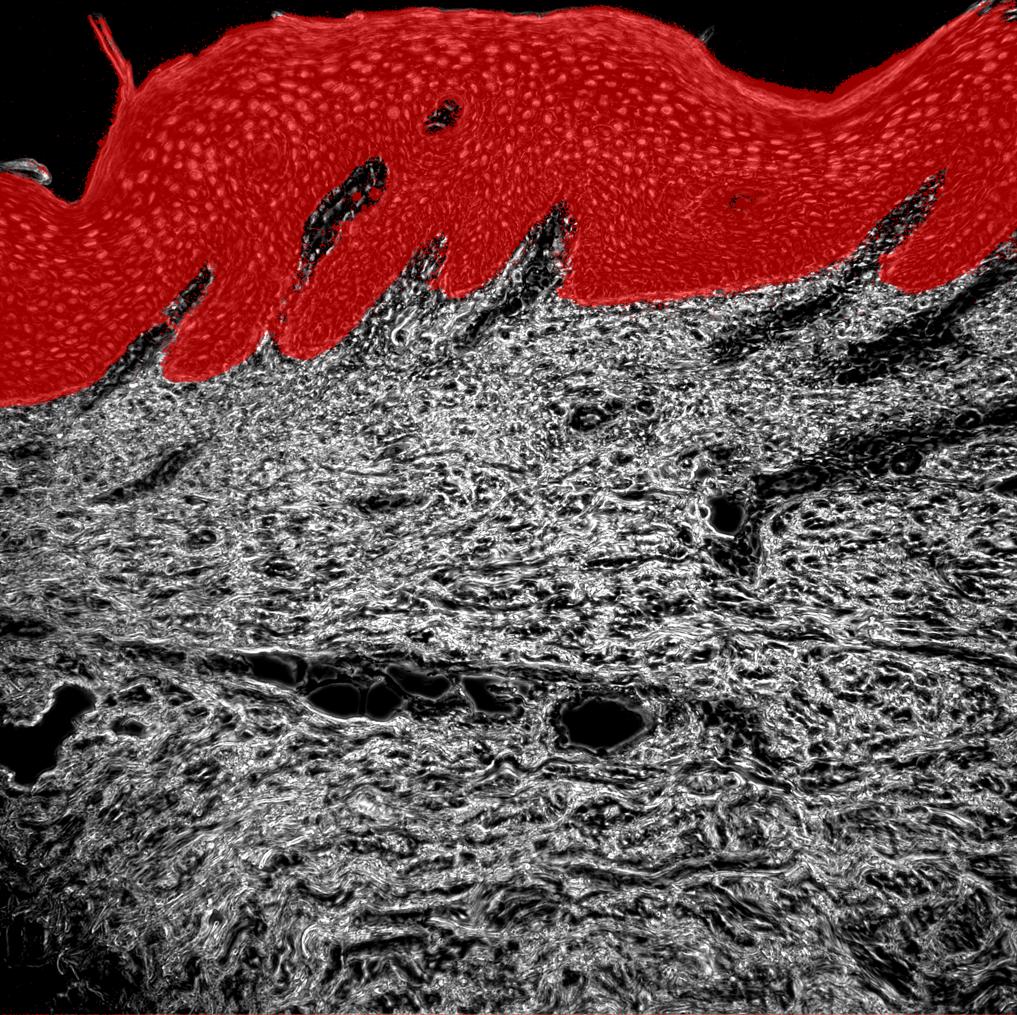

Phase contrast image

Keratinocytes

Psoriatic Skin

Human tissue section

Autoimmune loop